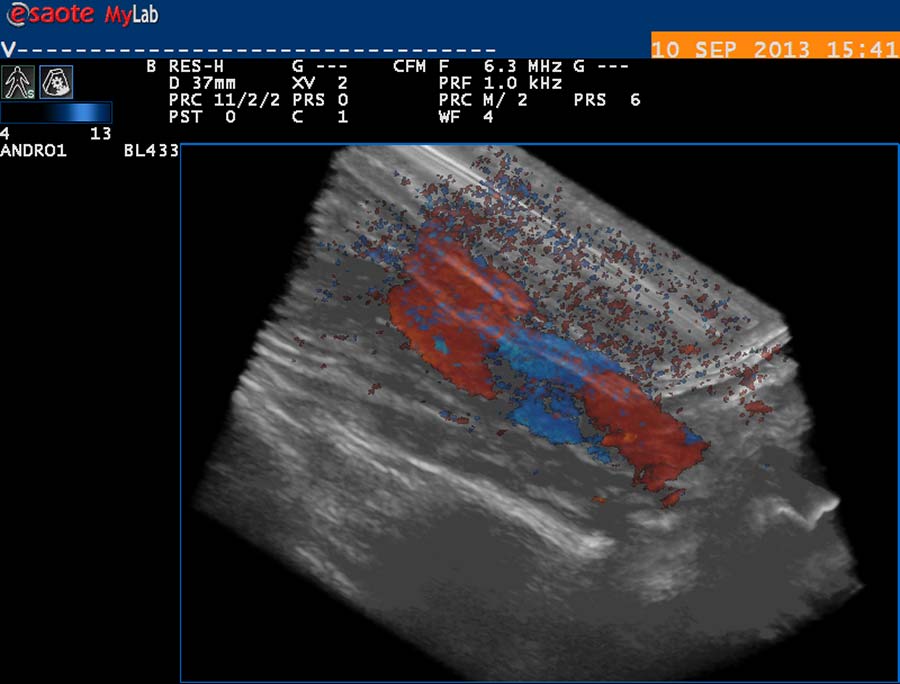

USG diagnostika vyžaduje odpovídající vybavení (obr. 12), zkušenosti a dostatek času. Vyšetření USG provádíme po termografickém vyšetření, na lůžku vyhřívaném na 30 st. Celsia, ultrasonografický gel zahříváme ve vodní lázni na teplotu 35 stupňů. Chladová kontrakce musculus cremaster vede k falešně negativním nálezům. Základní projekcí je koronární sken varlete (obr. 14) následovaný volumometrií ve dvou rovinách (obr. 15). Již na těchto skenech varlete je patrné rozšíření intratestikulárních cév, lépe je však viditelné při harmonickém („tissue enhancement imaging – TEI“) zobrazení (obr. 16, 17), a při barevném Dopplerovském zobrazení (Power Doppler) s TEI (obr. 18) s měřením šíře stěny a lumen žíly. Objemné dilatované žíly pampiniformního plexu jsou velmi dobře patrné na kolorizovaném TEI zobrazení (obr. 19), kde je možné zachytit pohyb venózní krve v souvislosti s dechem, intraabdominálním (IAP) a intrathorakálním tlakem. Informaci o atrofizaci tkáně získáme ze záznamu deformace kontury tunica albuginea podložkou, kterou je měkká buničina vložená pod skrotum (obr. 20, obr. 21 s volumometrií). Triplexní Dopplerovský záznam umožní hodnotit délku žilního refluxu a rychlost proudu refluktující krve v inspiriu, reflux při zvýšení intraabdominálního tlaku (obr. 22,23). Duplexní Dopplerovský záznam při harmonickém zobrazení s kolorizací zachycuje senzitivně změnu rychlosti proudění při refluxu v inspiriu s navazujícím zvýšením rychlosti při IAP (obr 25). Významná je možnost zachycení refluxu při klidném dýchání (respirační reflux, obr. 26).

obr. 18